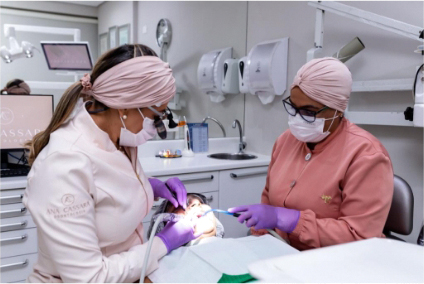

Saiba MaisTratamentos odontológicos que cuidam do seu sorriso

Tecnologias que te deixam com um sorriso no rosto!

Lupa examvision

Visualização perfeita de toda arcada dentária do paciente, aumentando a qualidade e precisão de diagnósticos e tratametos mais exigentes.

Microscópio operatório

Excelente visualização e luminosidade durante cirurgias, permitindo a avaliação das estruturas dos dentes e tecidos bucais.

O consultório em Alphaville

Já com uma equipe multidisciplinar, adotamos os protocolos mais utilizados na odontologia, aliado a uma estrutura pensada no conforto e privacidade para consultas personalizadas e diagnósticos precisos.

Com uma equipe engajada em priorizar a excelência no atendimento e o sorriso no rosto de quem mais importa: o paciente.